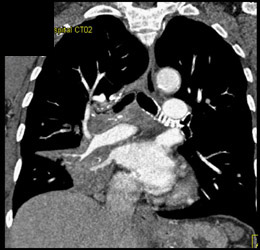

Pulmonary Nodule- Calcified